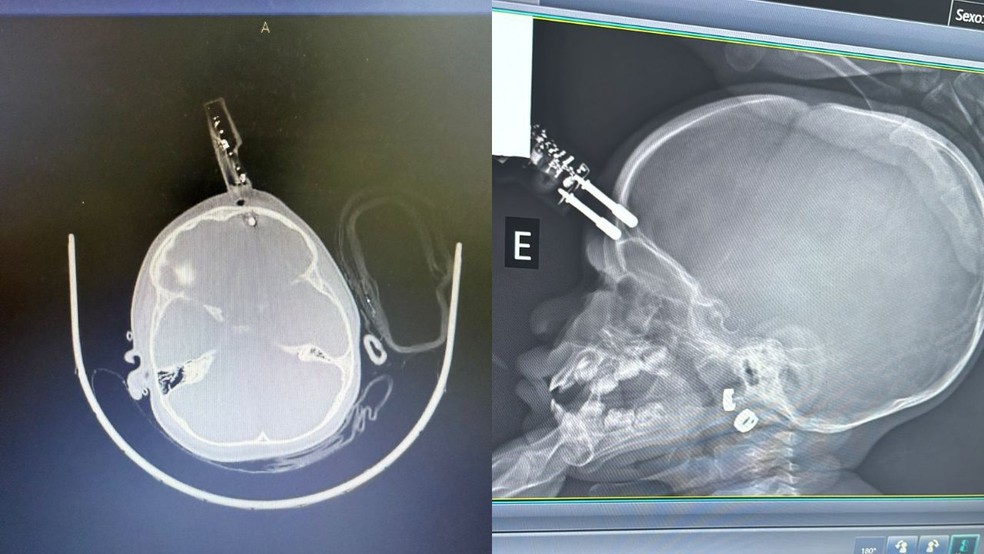

Menina fica com carregador cravado na cabeça em MG — Foto: Bruno Castro/Arquivo Pessoal

A principal hipótese, segundo o neurocirurgião, é que a menina estivesse com o carregador na mão no momento da queda. Por azar, o objeto atingiu a cabeça de forma que perfurou a região frontal do crânio, muito próxima ao olho.

Diante da gravidade do quadro, a criança foi levada imediatamente ao bloco cirúrgico do Complexo de Saúde São João de Deus (CSSJD), onde passou por procedimentos de limpeza, retirada do objeto, lavagem, fechamento e reconstrução da área atingida.